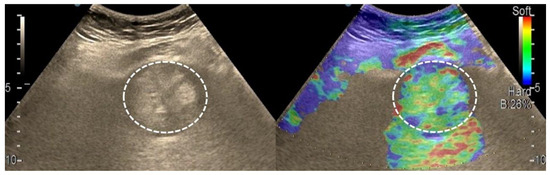

3.4. Real-Time Tissue Elastography

| Elasticity Type | Color Code |

|---|---|

| Type “a” | Homogenously green |

| Type “b” | Mosaic pattern with dominant green areas |

| Type “c” | Mosaic pattern with dominant blue areas |

| Type “d” | Homogenously light blue |

| Type “e” | Homogenously dark blue |

| RTE | Liver Adenoma | HMG | FNH | Complicated Liver Cyst | HCC | iCCA | Liver Metastases | Liver Lymphoma |

|---|---|---|---|---|---|---|---|---|

| Type “a” | 3 | 1 | ||||||

| Type “b” | 1 | 1 | 10 | 3 | 1 | |||

| Type “c” | 1 | 24 | 3 | 6 | ||||

| Type “d” | 1 | |||||||

| Type “e” | 5 | 3 | 1 |